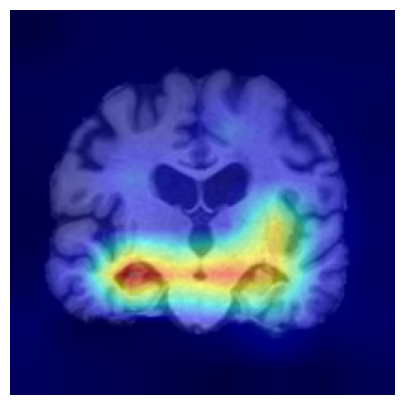

Results.

Figure 7 indicates the qualitative results. Our explainability method consistently highlights the hippocampal and medial temporal lobe regions, and the resulting heatmaps show strong correspondence with areas affected by hippocampal atrophy. These results supports that the identified regions align with established AD biomarkers.